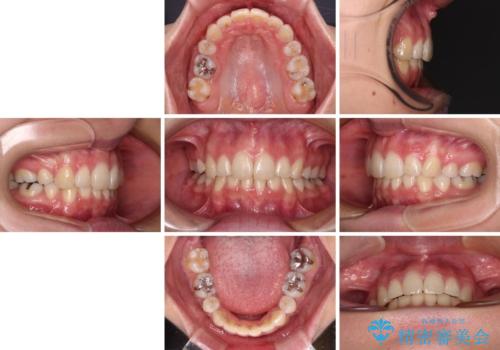

デコボコで飛び出した前歯 ワイヤー装置による抜歯矯正

- 上下前歯のデコボコと、飛び出した前歯を気にして来院された患者様です。

口元を積極的に引っ込めるために、上下左右の小臼歯計4本を抜歯することとしました。

咬み合わせが深く、咬合力強いため、補助装置を使用しながら積極的に口元を下げることとしました。

矯正治療前の咬み合わせで、前歯がすり減ってしまい、歯列が整ったときに先端がガタガタになってしまったため、矯正治療後に形態修正を行いました。